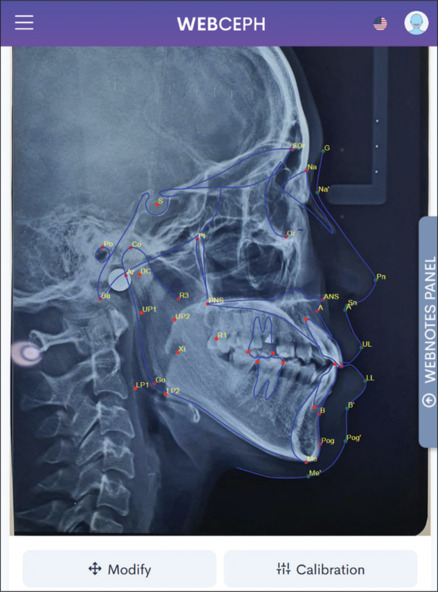

Objectives: To compare lateral cephalometric variables based on McNamara analysis between Indigenous and Chinese-Indonesian ethnic patients with skeletal class I malocclusion from Medan city.

Materials and methods: Simple random sampling of retrospective data from pre-treatment lateral cephalograms of orthodontic adult patients of three successive generations of the Mongoloid race in Medan from 2015 to 2023. Thus, the unpaired t-test and Mann-Whitney test were conducted after the normality test to compare the cephalometric analysis between Indigenous and Chinese-Indonesian ethnicities.

Results: This cross-sectional study analyzed 32 Indigenous and 34 Chinese ethnic lateral cephalograms. There were significant differences (P < 0.05) between Indigenous and Chinese ethnic in the lower pharynx, nasolabial angle, A to N perpendicular, maxillomandibular differential, and Pog to N Perpendicular variables for skeletal parameters. There were also significant differences (P < 0.05) in nasolabial angle for the soft tissue parameter and lower pharynx for the airway parameter. Conversely, there were no significant differences (P > 0.05) between these groups in the Co-A, Co-gnathion, lower anterior facial height (LAFH), facial axis angle, and mandibular plane angle for skeletal parameters. There were also no significant differences (P > 0.05) in upper incisor to A and lower incisor to A-Pog for dental parameters. Furthermore, there were also no significant differences (P > 0.05) in cant of the upper lip for soft tissue parameters and upper pharynx for airway.

Conclusions: It is advisable to consider certain landmarks and reference lines based on McNamara cephalometry parameters that showed a significant difference between Indigenous and Chinese ethnic groups with skeletal class I malocclusion when determining diagnosis and formulating individualized orthodontic treatment plans for multiethnic subpopulation patients in Medan.